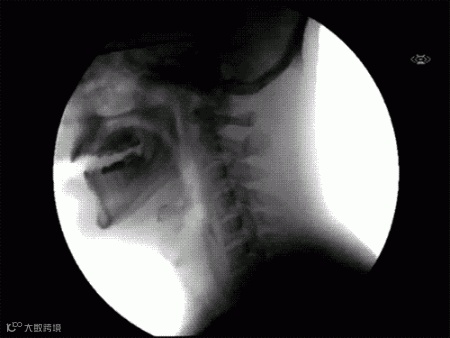

透视人类吞咽的生理过程。